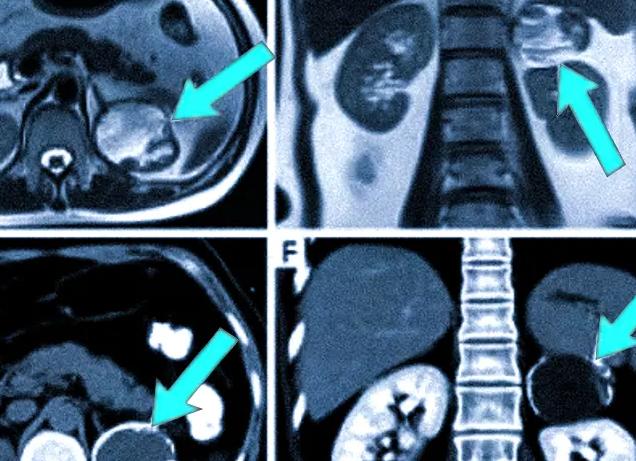

Ни для кого не секрет, что человеческое тело пронизано кровеносными сосудами, артериями, венами и капиллярами, которые являются неотъемлемой частью сердечного-сосудистой системы. Вне зависимости от места расположения каждая структурная единица данной системы очень важна для здоровья человека.